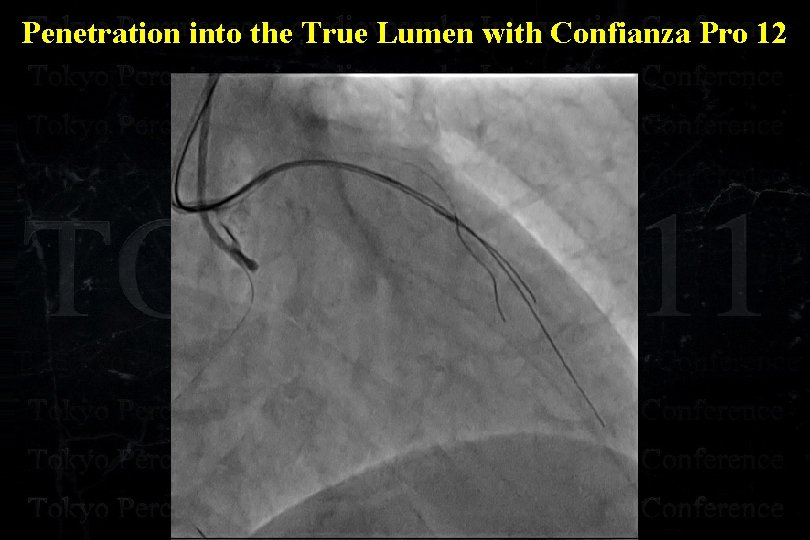

Penetration into the True Lumen with Confianza Pro 12

Penetration into the True Lumen with Confianza Pro 12

Penetration into the True Lumen with Confianza Pro 12